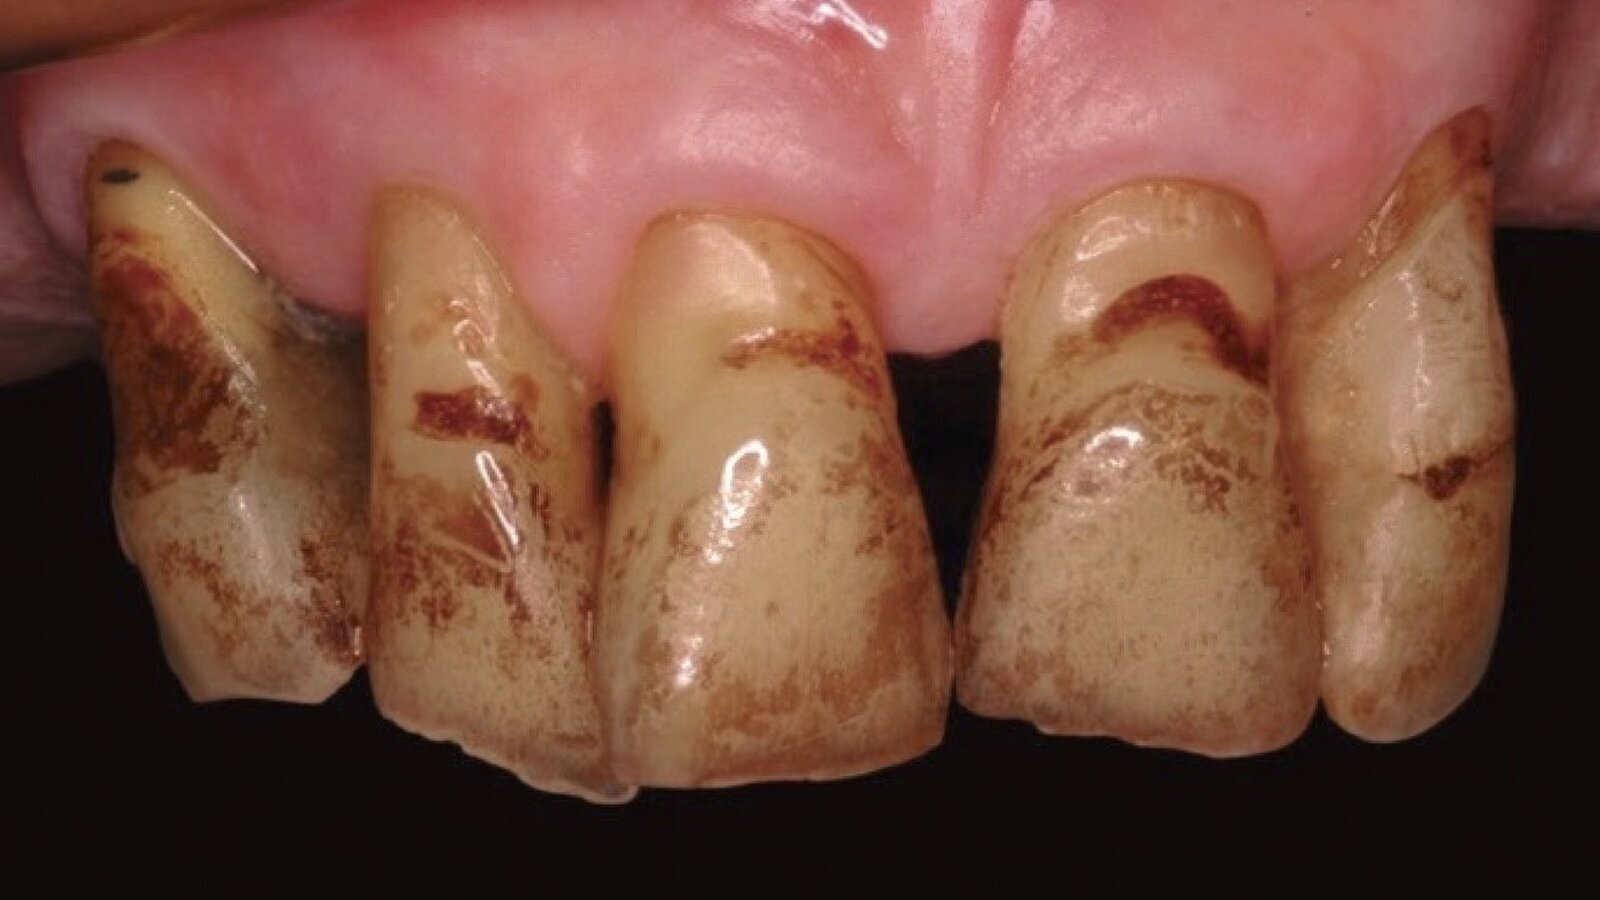

Figura 1. Las manchas externas causadas por pigmentación de nicotina son una de las causas más frecuentes de alteración del color dentario.

Pigmentaciones de origen extrínseco

Si dentro de los hábitos alimentarios de cada persona, reiteradas veces en el día y por períodos prolongados, se consumen bebidas y alimentos altamente pigmentarios, podría modificarse el color de las piezas dentarias, oscureciéndolas o generando manchas oscuras localizadas.

Este es el caso del té, café, bebidas artificiales, alimentos con colorantes, tabaco, vino tinto y algunos medicamentos como la clorhexidina.

El mecanismo químico que actúa en las pigmentaciones extrínsecas involucra la participación de fuerzas electrostáticas y de Van der Waals que actúan por mucho tiempo, así como también interacciones hidrofóbicas, fuerzas dipolo y puentes de hidrógeno que actúan por períodos cortos. Estas interacciones permiten al agente cromógeno o precromógeno alcanzar la superficie del diente y determinar la ocurrencia de la adhesión. Si la causa de la alteración de color es de origen extrínseco, es conveniente primero eliminar la misma y luego comenzar el tratamiento de blanqueamiento, ya que ningún blanqueador por intenso que sea puede evitar que el agente etiológico siga actuando sobre el diente.

A lo largo de este capítulo del libro se describe detalladamente el aspecto, ubicación, anamnesis y etiología de ese tipo de pigmentaciones. Las mismas son manchas de tabaco, manchas metálicas, manchas producidas por antibacterianos, y manchas de color marrón, verde, naranja o negro.